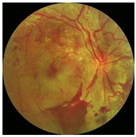

In this study, we used the Dataset for Diabetic Retinopathy (DDR) dataset [13], one of the fundus image datasets that became available to the public in 2019. This relatively new dataset contains 13,673 fundus images from 9598 patients collected from several hospitals in China in 2016–2018. DDR fundus images were collected from several different camera types using single-view and captured using the same technique. It consists of six categories, such as normal (6266 data), mild NPDR (630 data), moderate NPDR (4477 data), severe NPDR (236 data), PDR (913 data), and the undegradable images with poor quality (1151 data). It should be noted that classes are very unbalanced in the DDR datasets. The classification of unbalanced classes is challenging due to the highly skewed distribution of classes and the unequal costs of misclassification. Li, Gao, Wang, Guo, Liu, and Kang [13] state that lesions on the fundus image of mild NPDR are difficult to identify, and some severe NPDR classes are also easily misclassified as moderate NPDR. Therefore, we balanced this dataset by re-sampling using only three classes: normal, NPDR (mild, moderate, and severe classes were combined into one class), and PDR. Then, each class contains 913 data points, adjusting the amount of data in the PDR class with the distribution of training, validation, and testing data as described in Table 1. A sample of the DDR dataset is presented in Figure 4. It can be seen that there are no DR lesions on the normal retina. Retinal signs of NPDR can be observed in the presence of lesions, such as exudates, MAs, and HAs. Meanwhile, new blood vessels form in the retina affected by PDR (advanced DR cases).

Figure 4.

Example of DDR dataset: (a) normal; (b) NPDR; (c) PDR.